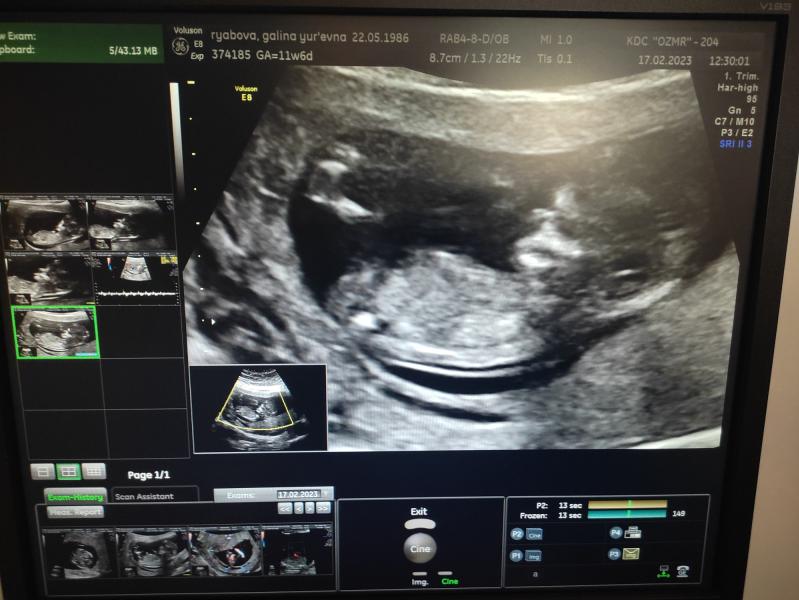

Сегодня ходила на первый скрининг! Врач никак не могла определить пол ребенка.Терпежа не хватает,как хочется знать.🥲🥲Может кто подскажет?😅

По вашему фото ничего не понятно ,врать не буду...моим прям "пипирку" приближали

На таком сроке не покажет. Только, в лучшем случае, после 13 недель и то, хороший специалист, т.к там нет ещё половых органов, а только небольшой бугорок у мальчиков😄

У вас фотка не между ног даже))) тут не определишь. На втором скажут точно, либо кровь сдать

Сдайте кровь на определение пола, на первом скрининге пол еще не возможно определить, только предположить